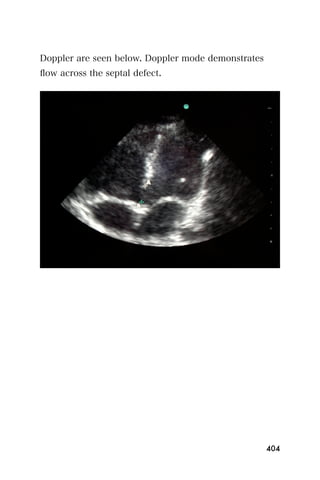

the ultrasound probe low on the patient s abdomen, just

above the pubic bone, in a sagital position. Identify the